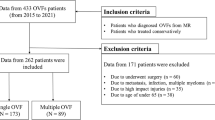

This was a multicenter cohort study in 11 institutions [18]. From 2012 to 2015, 153 patients with symptomatic osteoporotic vertebral fractures were followed up for 6 months after the onset of osteoporotic vertebral fractures. The inclusion criteria were age of > 65 years, diagnosis of a recent osteoporotic vertebral fracture, and back pain onset within 2 weeks prior to presentation. The exclusion criteria were pathological fractures, multiple fractures, malignant cancer, dementia, and high-energy injury.

Among the 153 eligible patients, 40 patients were excluded because of the lack of MRI data including axial T2-weighted image at L3. As a result, 117 patients (92 women and 25 men) with a mean age of 78.5 years (standard deviation 7.4) were finally analyzed.